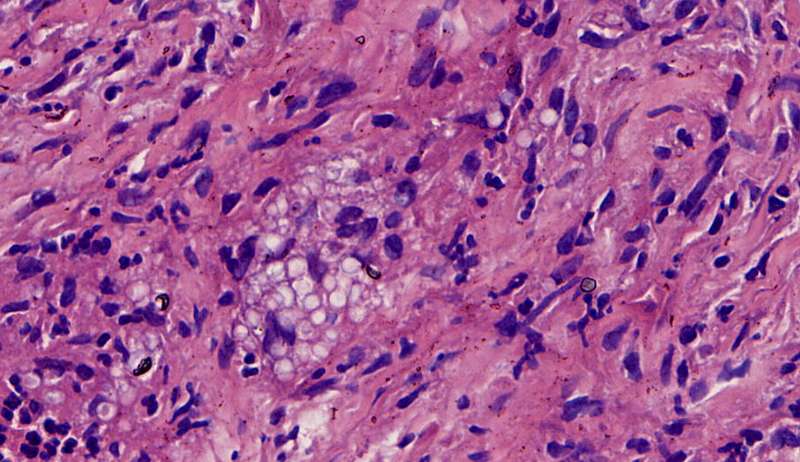

隐球菌

结节状,周围型,宽基底,巨噬细胞多而且大,有纤维组织,所以经常有点收缩力

这些就是隐球菌,常被巨噬细胞吞噬,大多为多核巨噬细胞 隐球菌感染,在免疫力正常情况下,就是个肉芽肿 小白球,略显淡蓝色,这是荚膜的感觉

隐球菌在HE染色是小白球,隐隐的,球状的。在PAS染色是红色的小球,在六铵银染色是黑褐色的小球。